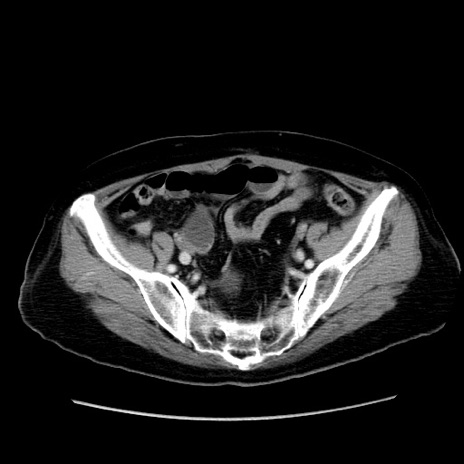

症例19(横断像)

【症例】80歳代女性

【主訴】下腹部痛

【現病歴】約8時間前より下腹部痛の出現あり、救急外来受診。

【既往歴】両側付属器切除

【身体所見】意識清明、下腹部正中に手術痕あり、その部位に一致して圧痛と反跳痛あり。腸蠕動音は亢進。

【データ】WBC 9300、CRP 0.15